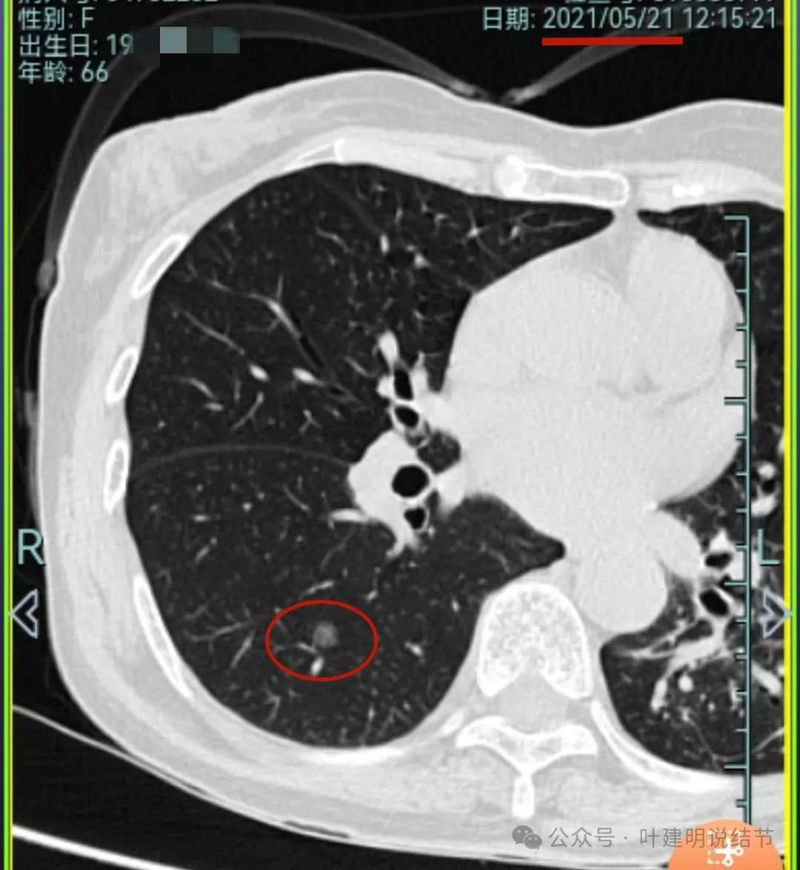

再看2021年随访的影像:

病灶1似乎中间高密度部分略有密度增高。

病灶2与2019年时相仿。

病灶3仍是混合密度,进展不显著。

病灶4仍是伴钙化的,也没有明显进展。

病灶5较前密度略显杂乱,整体密度应该有所增高。

病灶6轮廓较前清楚,灶内有血管穿行,也有轻微胸膜牵拉。

原病灶7已经被切除。